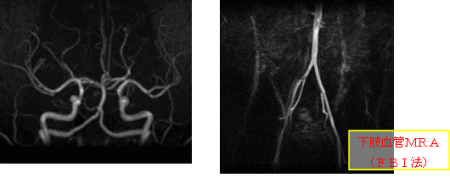

MRA

MRIを使って血管のみを抽出するように撮影する方法をMRA(MRアンギオグラフィ)といいます。

MRAには、造影剤を使用して撮影する方法と、使用しない撮影方法とがあります。頭部や頸部、下肢の血管は比較的造影剤を使用しません。